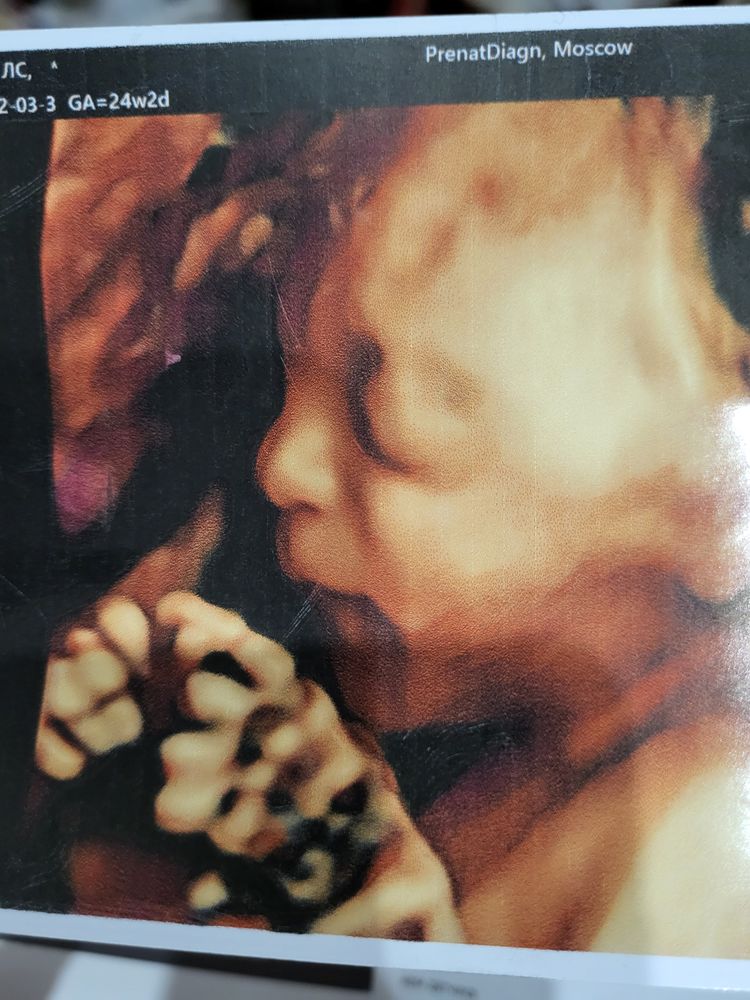

Тут срок 24+6, лежала не очень удобно для хорошего снимка) щеки вроде есть, но и вес у нее тогда был 850 гр